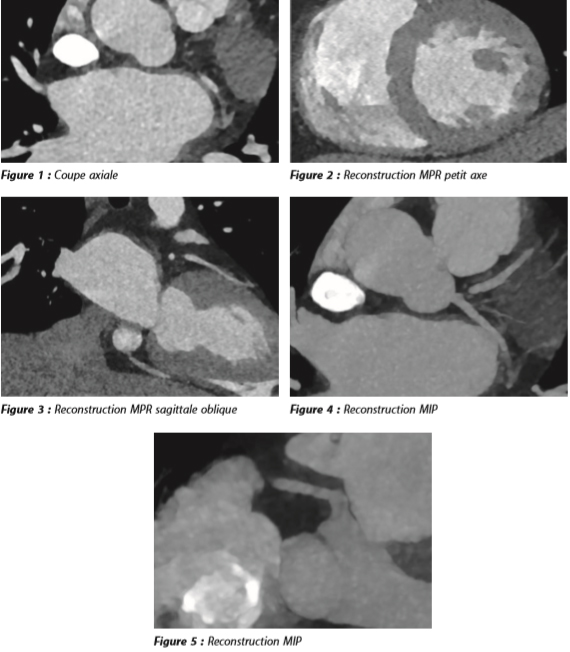

Il est décidé de ne pas aller en salle de cathétérisme, mais de réaliser un scanner cardiaque synchronisé à l'ECG dont voici quelques coupes.

Pont myocardique profond de l'artère coronaire interventriculaire antérieure dans sa portion moyenne.

Les images montrent la présence d'une plage de tissu de densité myocardique engainant de manière circonférentielle la portion moyenne de l'IVA (fig. 6a). La coupe sagittale dévoile bien la course intra-myocardique de l'IVA sur environ 15 mm et d'une profondeur de 3mm (fig. 6b), par opposition au trajet épicardique normal de la coronaire droite et du tronc commun gauche. Cette anomalie correspond donc à ce que l'on appelle un pont myocardique qui est susceptible d'expliquer l'épisode angineux. Par ailleurs, le coroscanner n'a pas révélé de coronaropathie.

Figure 7 : Visualisation du pont myocardique sur la reconstruction curviligne dans l'axe du vaisseau (a). En diastole (b), le myocarde relâché ne sténose pas de l'artère coronaire, alors qu'il la sténose en systole (c).

Il est très rarement symptomatique. Sur un coroscanner, il faut préciser (fig. 8) :

• le segment artériel concerné ;

• la longueur du pont ;

• et la profondeur, c'est-à-dire l'épaisseur de myocarde entre la paroi artérielle la plus superficielle et la graisse épicardique.